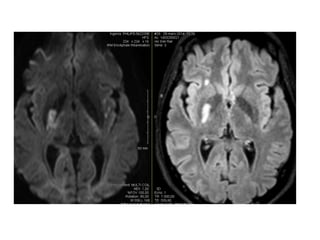

Mismatch diffusion-FLAIR

• Il est 7h30… Attente de

l’hémostase

• 7h45 : INR = 1,47

• Thrombolyse intraveineuse faite aux

• Infarctus sylvien gauche étendu

• Présence d’un mismatch Diffusion/FLAIR

MAIS